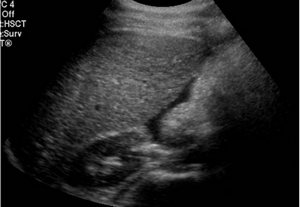

Ультразвуковое исследование при этом не дает визуальных положительных результатов беременности, то есть, на экране аппарата не выявляется наличие плодного яйца в матке. Лечится внематочная беременность исключительно хирургическим путем. Операция заключается в удалении маточной трубы с оплодотворенной яйцеклеткой. После чего, женщине не рекомендуется беременеть в течение первых трех лет. Нередко боли внизу живота на ранних стадиях беременности происходят из-за наличия заболеваний мочевыделительной системы. Цистит (воспаление в мочевом пузыре), заболевание, которое наиболее часто встречается у беременных. Его также путают с частым мочеиспусканием при беременности.

- УЗИ матки с целью выявления патологий в ее структуре.